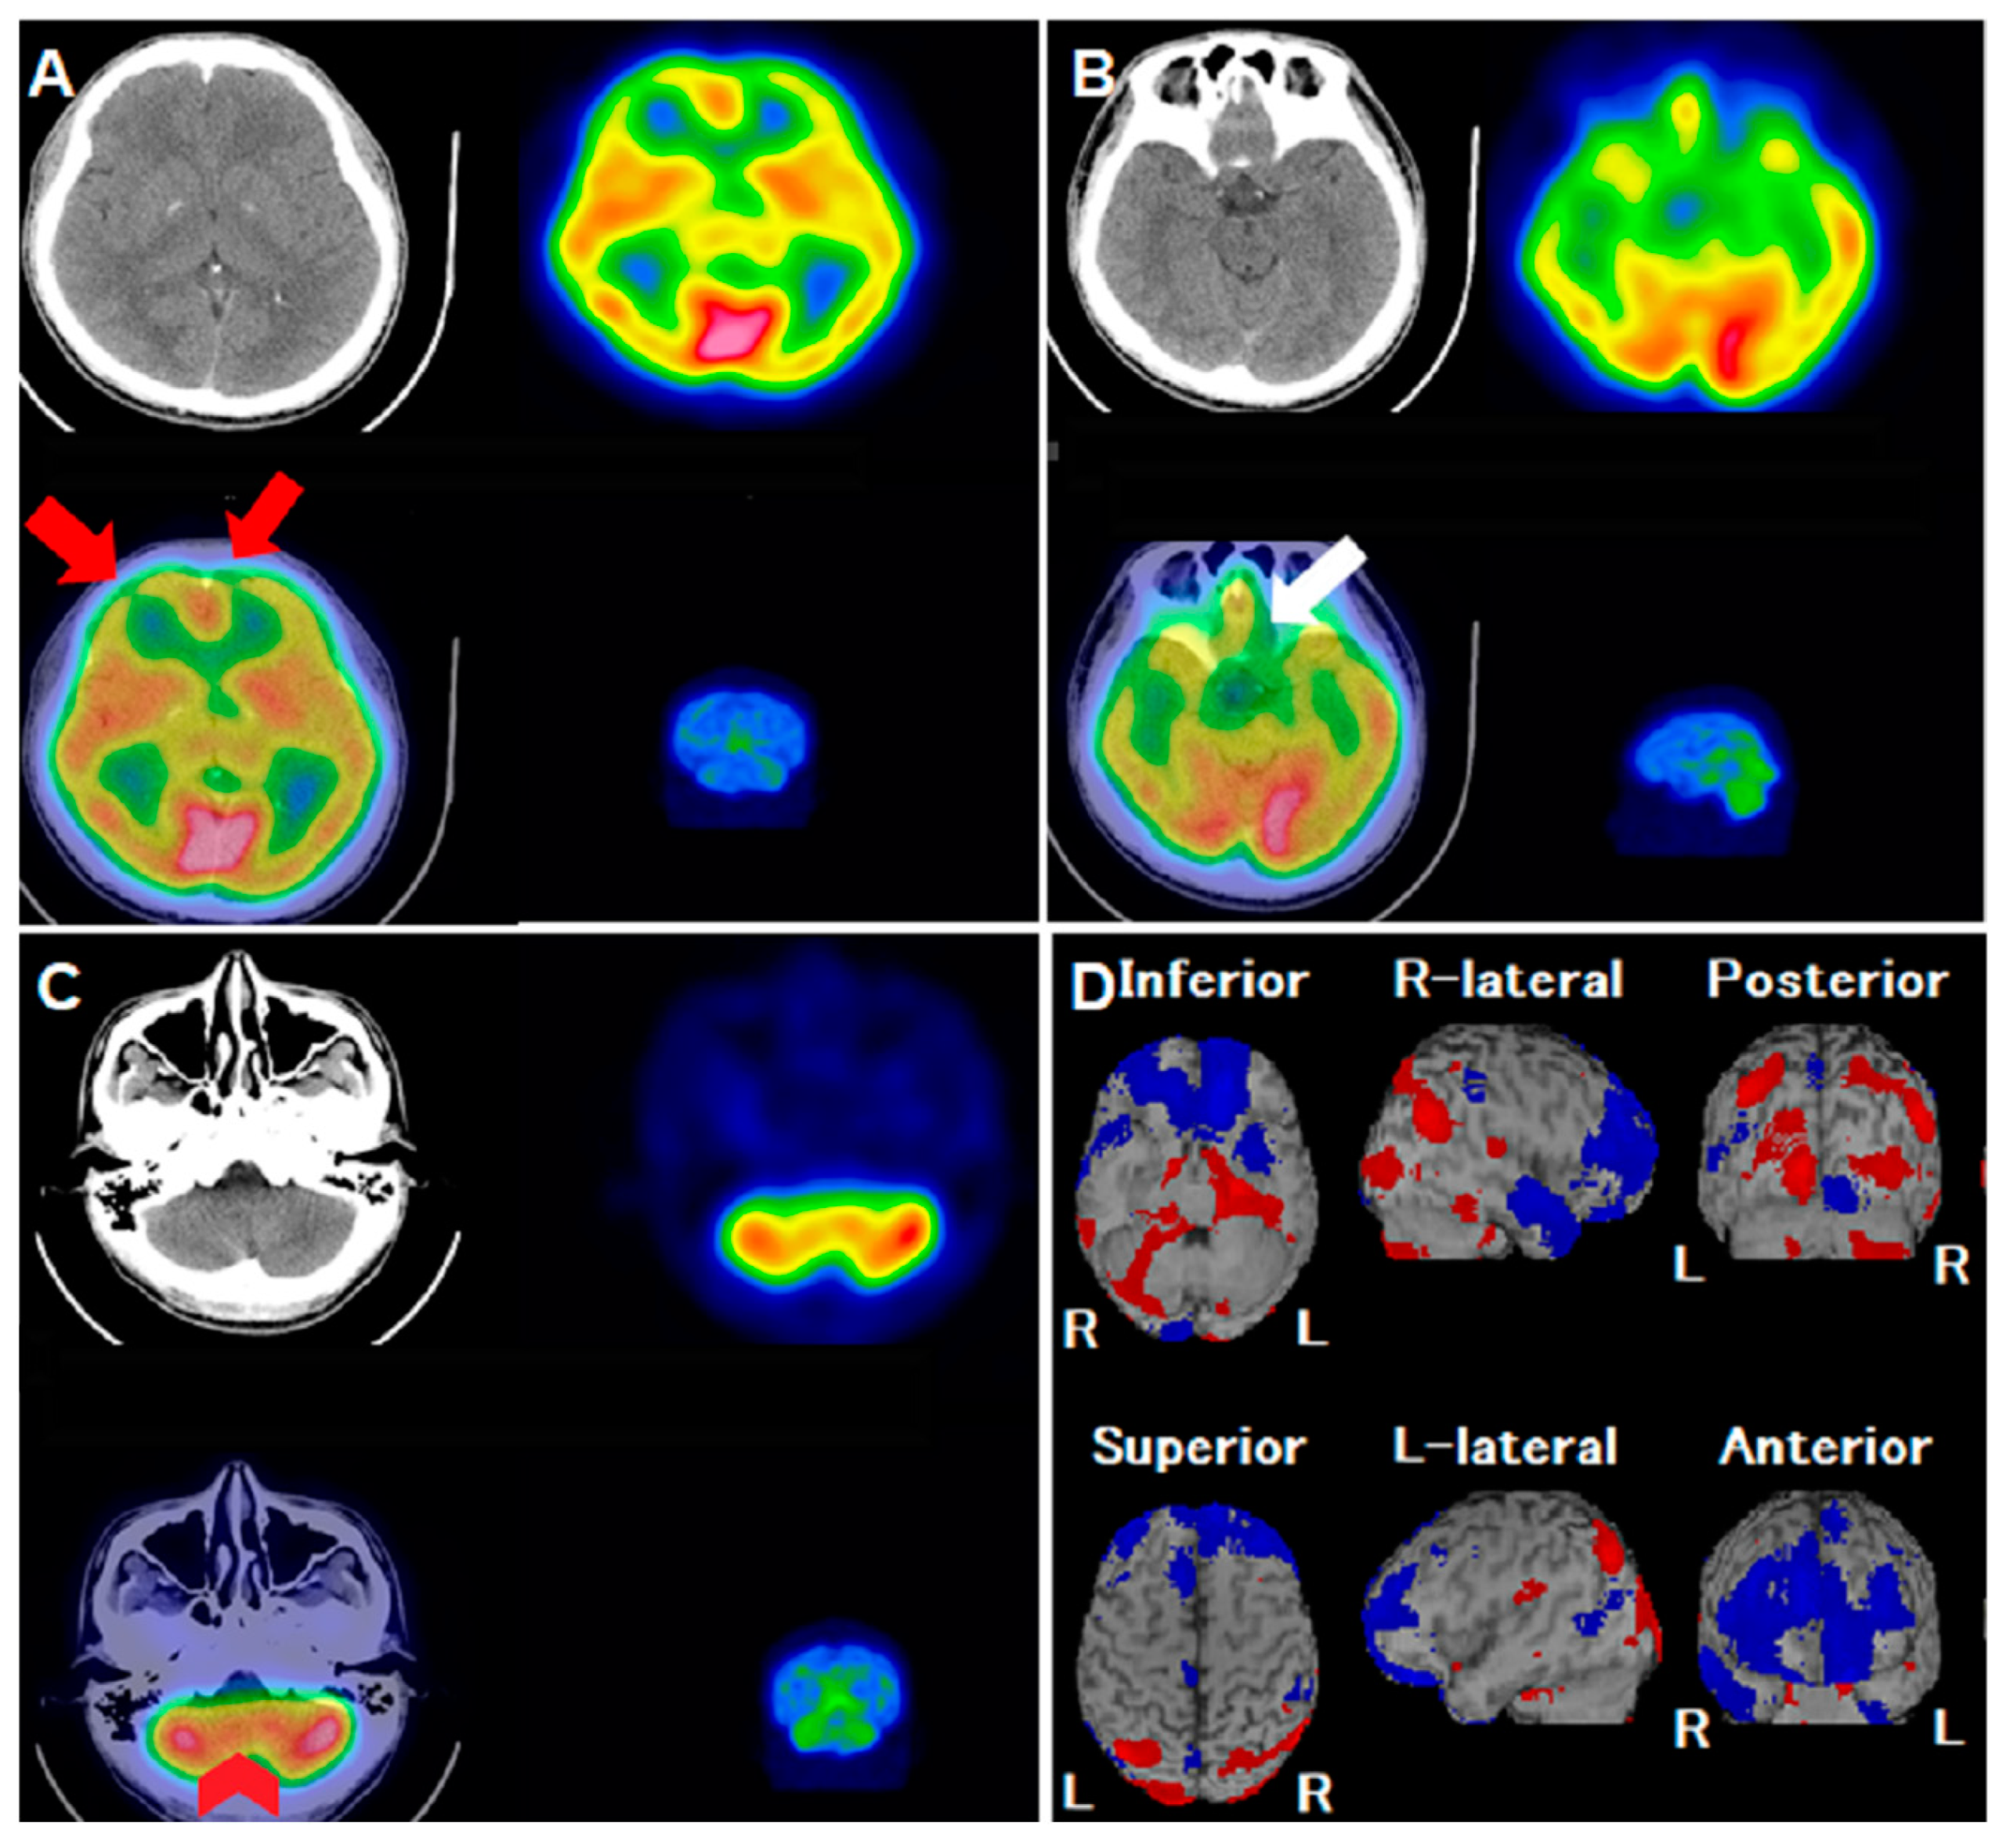

Figure 1.

A 31-year-old man experienced intermittent headaches and lower back pain, particularly during work. Despite the progression of his symptoms, a conventional CT scan did not show any abnormalities. To assess possible neurological or psychological causes, his physician recommended a 99mTc-ethyl cysteinate dimer (ECD) single-photon emission computerized tomography/computerized tomography (SPECT/CT). However, after undergoing the SPECT/CT examination, the patient developed severe rhinorrhea, sore throat and general malaise several hours later. He was subsequently diagnosed with COVID-19 (SARS-CoV-2) and consistently reported a diffuse headache along with an uneven sensation of fullness in his head, though he had no visual, sensory, or balance disturbances. The patient reported chronic tension headache for long time. However, during COVID infection period, headache was more severe than he ever experienced. Pain was accompanied with band-like tightness and diffuse fullness sensation, without nausea, vomiting, pulsatile sensation, photophobia or phonophobia. There was no autonomic symptoms including lacrimation, miosis, or redness of the eye. Symptoms lasted for about 1 week. After recovery from COVID-19 infection, there was no residual neurological deficit. A review of the 99mTc-ECD SPECT images revealed hypoperfusion defects in the bilateral frontal lobes ((A), axial views; red arrows) and the olfactory cortex ((B), axial views; white arrow). There was also asymmetrical perfusion activity in both cerebellum hemispheres ((C), axial views; red arrowheads), with no corresponding structural abnormalities. An additional analysis using the Easy Z-score imaging system (eZIS) highlighted a significant reduction in regional cerebral blood flow (rCBF), prominently in the bilateral middle/inferior frontal gyri and bilateral olfactory sulci ((D), blue-colored areas), contrasted by hyperperfusion in the occipital lobe. This case highlights the regional brain perfusion abnormalities identified by 99mTc-ECD SPECT/CT in a patient infected with COVID-19. Despite presenting with headaches, the patient showed no structural abnormalities, underscoring the potential neurological implications of the disease.